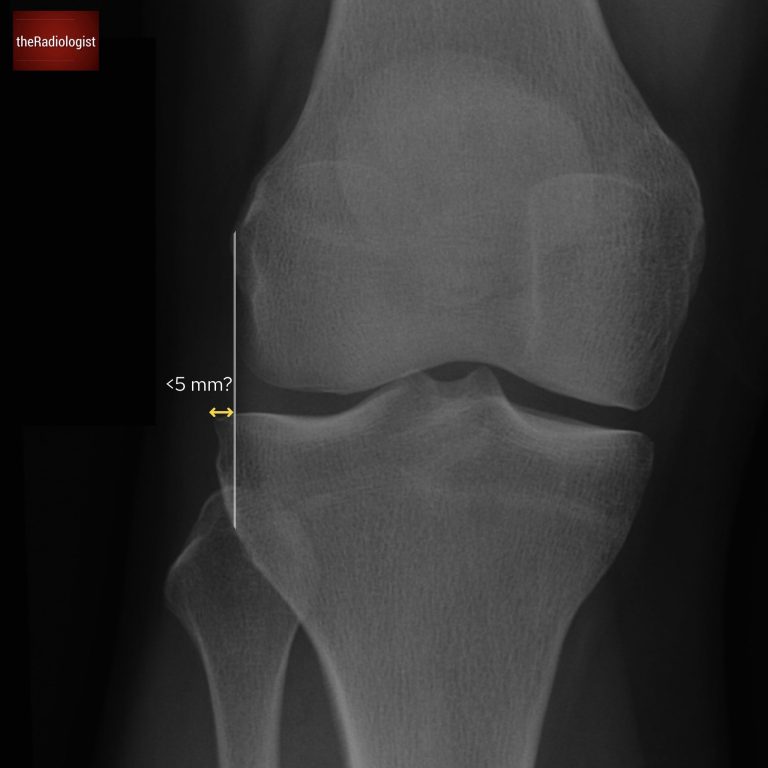

Draw a vertical line down the most lateral margin of the femur. You should only see a maximum of 5 mm of the tibia to the lateral aspect of this line. If there is more than this, ie. there’s too much of the tibia that’s lateral, then suspect a fracture of the lateral tibial plateau.

Draw a line down from the most lateral margin of the femur and you should only see a maximum of 5 mm of the tibia lateral to this line.